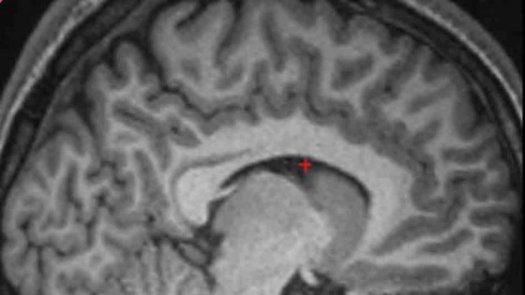

前脑一个被称为“副扣带沟(PCS)”的摺痕显然可以帮助人们更准确记住事情是想像出的还是真实发生了,或记住真正说话的是哪个人。据剑桥大学的研究人员称,这是人类出生前最后长出的几条结构性褶皱之一,而且每个人的大小迥异。研究人员说,有这种褶皱的人记忆力要比没有的人强许多。

参加者是根据核磁共振扫描成像来挑选的。从图像上可以清楚地看到他们是否有PCS褶皱。随后,让他们看结对和半结对的词———如“Laurel和Hardy”和“Laurel和?”。在第二轮测试中,要求他们想像另一个词,随后要么是他们,要么由研究负责人真正大声说出这个词。

A Specific Brain Structural Basis for Individual Differences in Reality Monitoring

Much recent interest has centered on understanding the relationship between brain structure variability and individual differences in cognition, but there has been little progress in identifying specific neuroanatomical bases of such individual differences. One cognitive ability that exhibits considerable variability in the healthy population is reality monitoring; the cognitive processes used to introspectively judge whether a memory came from an internal or external source (e.g., whether an event was imagined or actually occurred). Neuroimaging research has implicated the medial anterior prefrontal cortex (PFC) in reality monitoring, and here we sought to determine whether morphological variability in a specific anteromedial PFC brain structure, the paracingulate sulcus (PCS), might underlie performance. Fifty-three healthy volunteers were selected on the basis of MRI scans and classified into four groups according to presence or absence of the PCS in their left or right hemisphere. The group with absence of the PCS in both hemispheres showed significantly reduced reality monitoring performance and ability to introspect metacognitively about their performance when compared with other participants. Consistent with the prediction that sulcal absence might mean greater volume in the surrounding frontal gyri, voxel-based morphometry revealed a significant negative correlation between anterior PFC gray matter and reality monitoring performance. The findings provide evidence that individual differences in introspective abilities like reality monitoring may be associated with specific structural variability in the PFC.